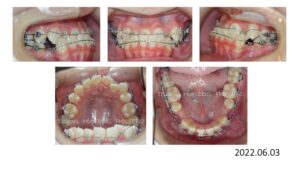

検査、診断の結果、上下顎前突と診断、上顎両側4番、下顎両側5番を抜歯し、患者さんの希望により、舌側矯正で治療を開始しました。

埋伏している 8番は抜歯を依頼しました。

治療開始から 1年 4ヶ月で抜歯空隙は既に閉鎖し、細部の仕上げに入ります。

治療終了時の写真です。

動的治療期間は、1年 5か月です。

上顎前歯は 8㎜、下顎前歯は 4㎜後退し、口が閉じれないという主訴も改善されました。